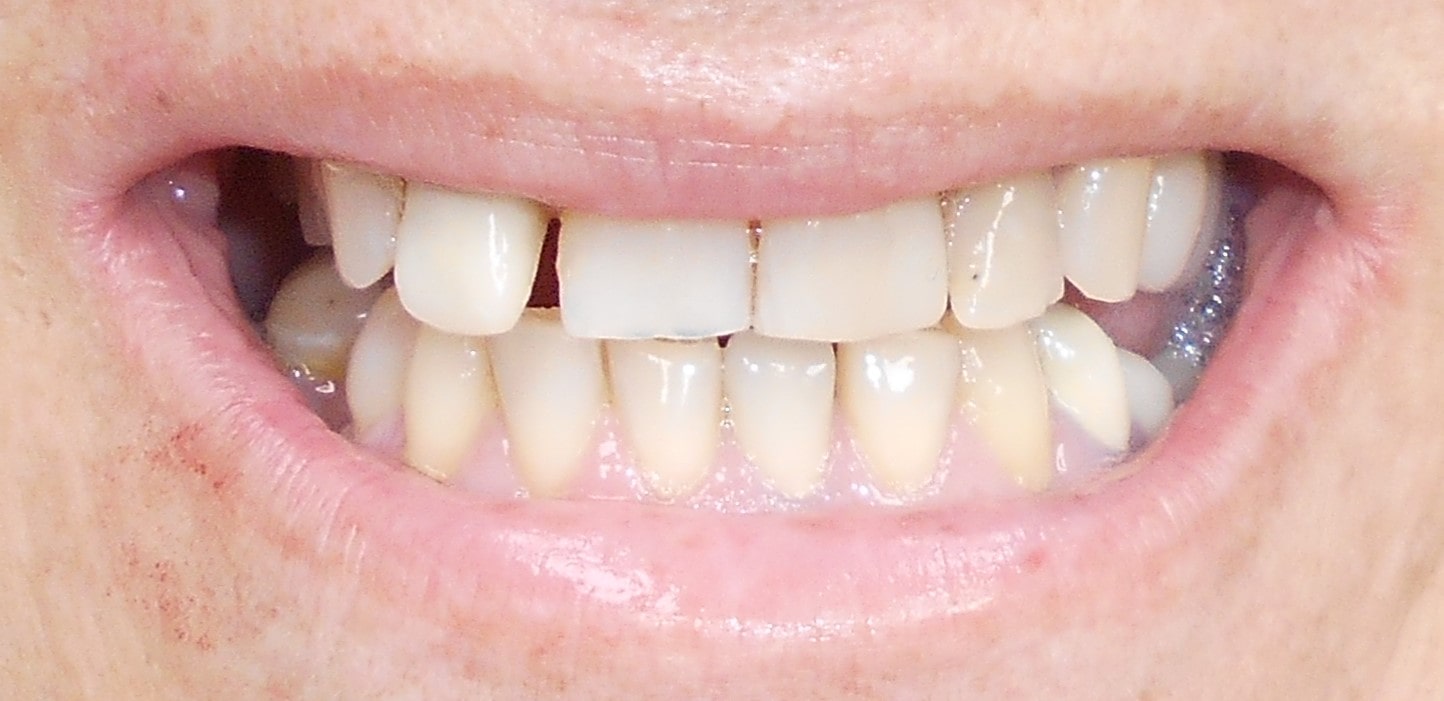

Pacijent 5

Pacijent kod koga je rađena kombinacija rešavanja bezubih prostora sa ugradnjom implantata, a nakon tri meseca kompletno rešavanje sa cirkonijum keramičkim -bezmetalnim krunica i mostovima.